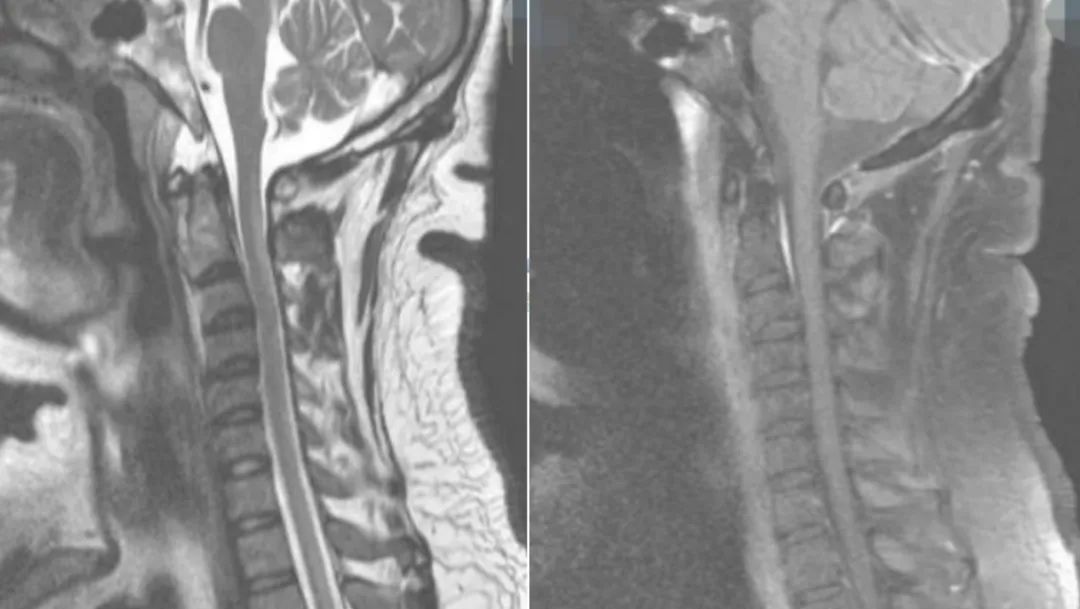

男性34岁,肢体麻木无力1月余入院。查体:神志清,双上肢肌力5级,双下肢4+级,远端4级,左上肢触觉轻度减退,双下肢触痛觉,振动觉明显减退,外院激素冲击治疗5天症状无改善。

答案:脊髓亚急性联合变性。维生素B12摄取、吸收、结合与转运的任何一个环节出现障碍均可引起维生素B12缺乏。内因子抗体和(或)抗胃壁细胞抗体阳性的SCD患者需要长期肌肉注射维生素B12。笑气中毒也是脊髓亚急性联合变性的重要原因,需要注意个人生活接触史。除了经典的反兔耳征/八字征/倒Ⅴ字征,脊髓亚急性联合变性还能够表现为圆点征、小字征、三角征。脊髓亚急性联合变性还需要与铜缺乏性脊髓病、维生素E缺乏性脊髓病、艾滋病相关性脊髓病鉴别。